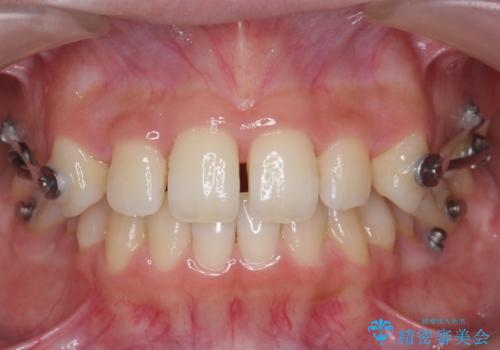

歯を抜かない矯正 出っ歯を抜かずに大きく下げることは可能です。

- 出っ歯を主訴に来院。

上の歯を全体に大きく後ろに下げる治療計画を立てました。

後ろに下げるために、親知らずは抜歯しています。

後ろに下げるために、ワイヤー矯正の前にカリエールという装置を使用しました。